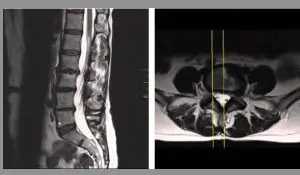

È importante consultare uno specialista in radiologia interventistica o un neurochirurgo per diagnosticare e trattare correttamente il dolore discogeno. La diagnosi può essere supportata tramite tecniche avanzate di imaging, come la risonanza magnetica (RM) o la tomografia computerizzata (TC), che permettono di osservare in dettaglio la condizione dei dischi e delle strutture circostanti.